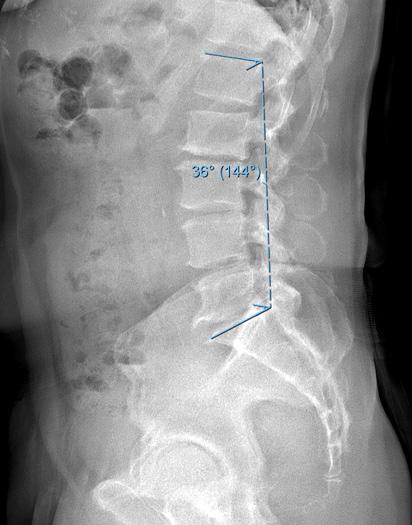

Figure. (A) Preoperative and (B) 6-month postoperative lateral radiographs demonstrating change in lumbar lordosis after isolated decompression.

Madkouri et al also showed severe preoperative imbalance, SVA greater than 100 mm, was predictive of persistent imbalance after surgery.17 Salimi et al similarly reported longer term alignment outcomes after isolated decompression, also finding that LL significantly increased while SVA decreased at 2 and 5 years postoperatively. 9 Overall, 42.6% of patients with preoperative malalignment developed normal alignment postoperatively, maintaining proper alignment up to the 5-year follow-up. In this cohort, postoperative malalignment was associated with significantly worse VAS back pain scores at long-term follow-up. These findings are consistent with those of Hikata et al and Ogura et al, who reported similarly sustained transitions to improved sagittal alignment following isolated decompression of 52.3% and 44.8%, respectively, at 2-year follow-up. 12,13 Ogura et al further reported that continued positive postoperative SVA had negative implications on clinical outcomes and patient-reported quality of life. Along with improvements in sagittal alignment, Bouknaitir et al found significant concomitant reductions in PI-LL at 6-month follow-up, which

was further studied by Minamide et al and Chang’s report of LSS patients being more likely to have satisfactory clinical outcomes with decompression alone if the PI-LL mismatch is minimized. 18–20 A separate analysis by Chang demonstrated a correlation of 10° increase in lumbar lordosis after decompression surgery was associated with a 5-point improvement in physical function scores. 21